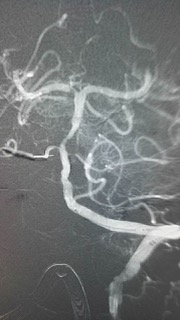

术中见患者基底动脉上段闭塞,典型的基底动脉尖综合征。基底动脉尖综合征是一种潜在的致命性神经系统疾病,进展极快,临床医生诊断和治疗该病面临很大挑战,其约占所有缺血性卒中的 1%-4%,死亡率更是高达75%。

术中结果不容乐观,如果基底动脉闭塞不处理,患者随时可能出现中枢性呼吸循环衰竭导致死亡。

目前最适合的救治办法是短时间内取出血栓,方能恢复脑血管血供,恢复患者神经功能。

脑动脉机械取栓术听起来简单,但操作起来难度颇大。其操作方法是:股动脉穿刺置入一根细细的导管,缓慢上行至脑血管,精确定位后再次置入一个取栓导丝,释放导丝,让导丝包裹血栓,再像拔红酒瓶塞一样回收导丝,取出血栓。

手术要求的精细度极高,对操作者的技术水平、熟练程度、心理素质、团队协作等都是极大的考验。江顺福主任都是有着多年血管介入临床经验的介入专家,血管内技术炉火纯青;吴明超副主任医师则刚刚从南京学了脑动脉取栓技术回到神经内科,对脑梗塞的治疗相当娴熟。两位专家充分运用纯熟的血管介入技术,密切配合,终于顺利取出了盘居在脑动脉内的“夺命血块”。经过1个多小时的紧张手术后,成功取出栓子,患者闭塞的基底动脉开通,术后安返病房严密监测及术后的继续治疗。术后24小时患者神志转清,能回答问题,家属非常感动。